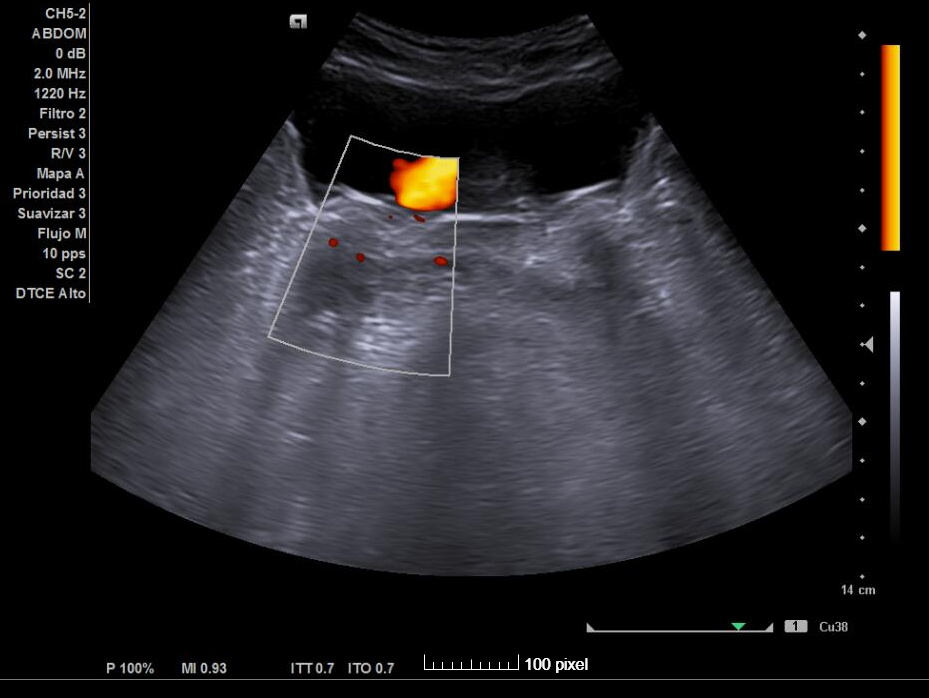

Por este motivo se solicita ecografía clínica para valorar la vía urinaria.

Ecografía clínica urinaria:

Diagnóstico: ureterectasia con ureteroceles bilaterales.